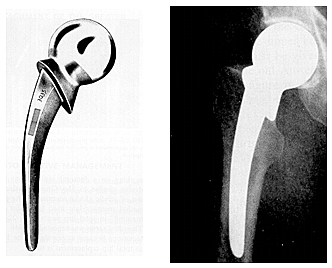

• Reemplazo de cadera, diseño endoprotesis Thompson

Reemplazo de cadera, diseño endoprotesis Thompson

Prótesis metálicas con vástagos medulares para la fijación esquelética. Desarrollados en Estados Unidos por Fred Thompson. Para fijación a presión dentro del canal medular.